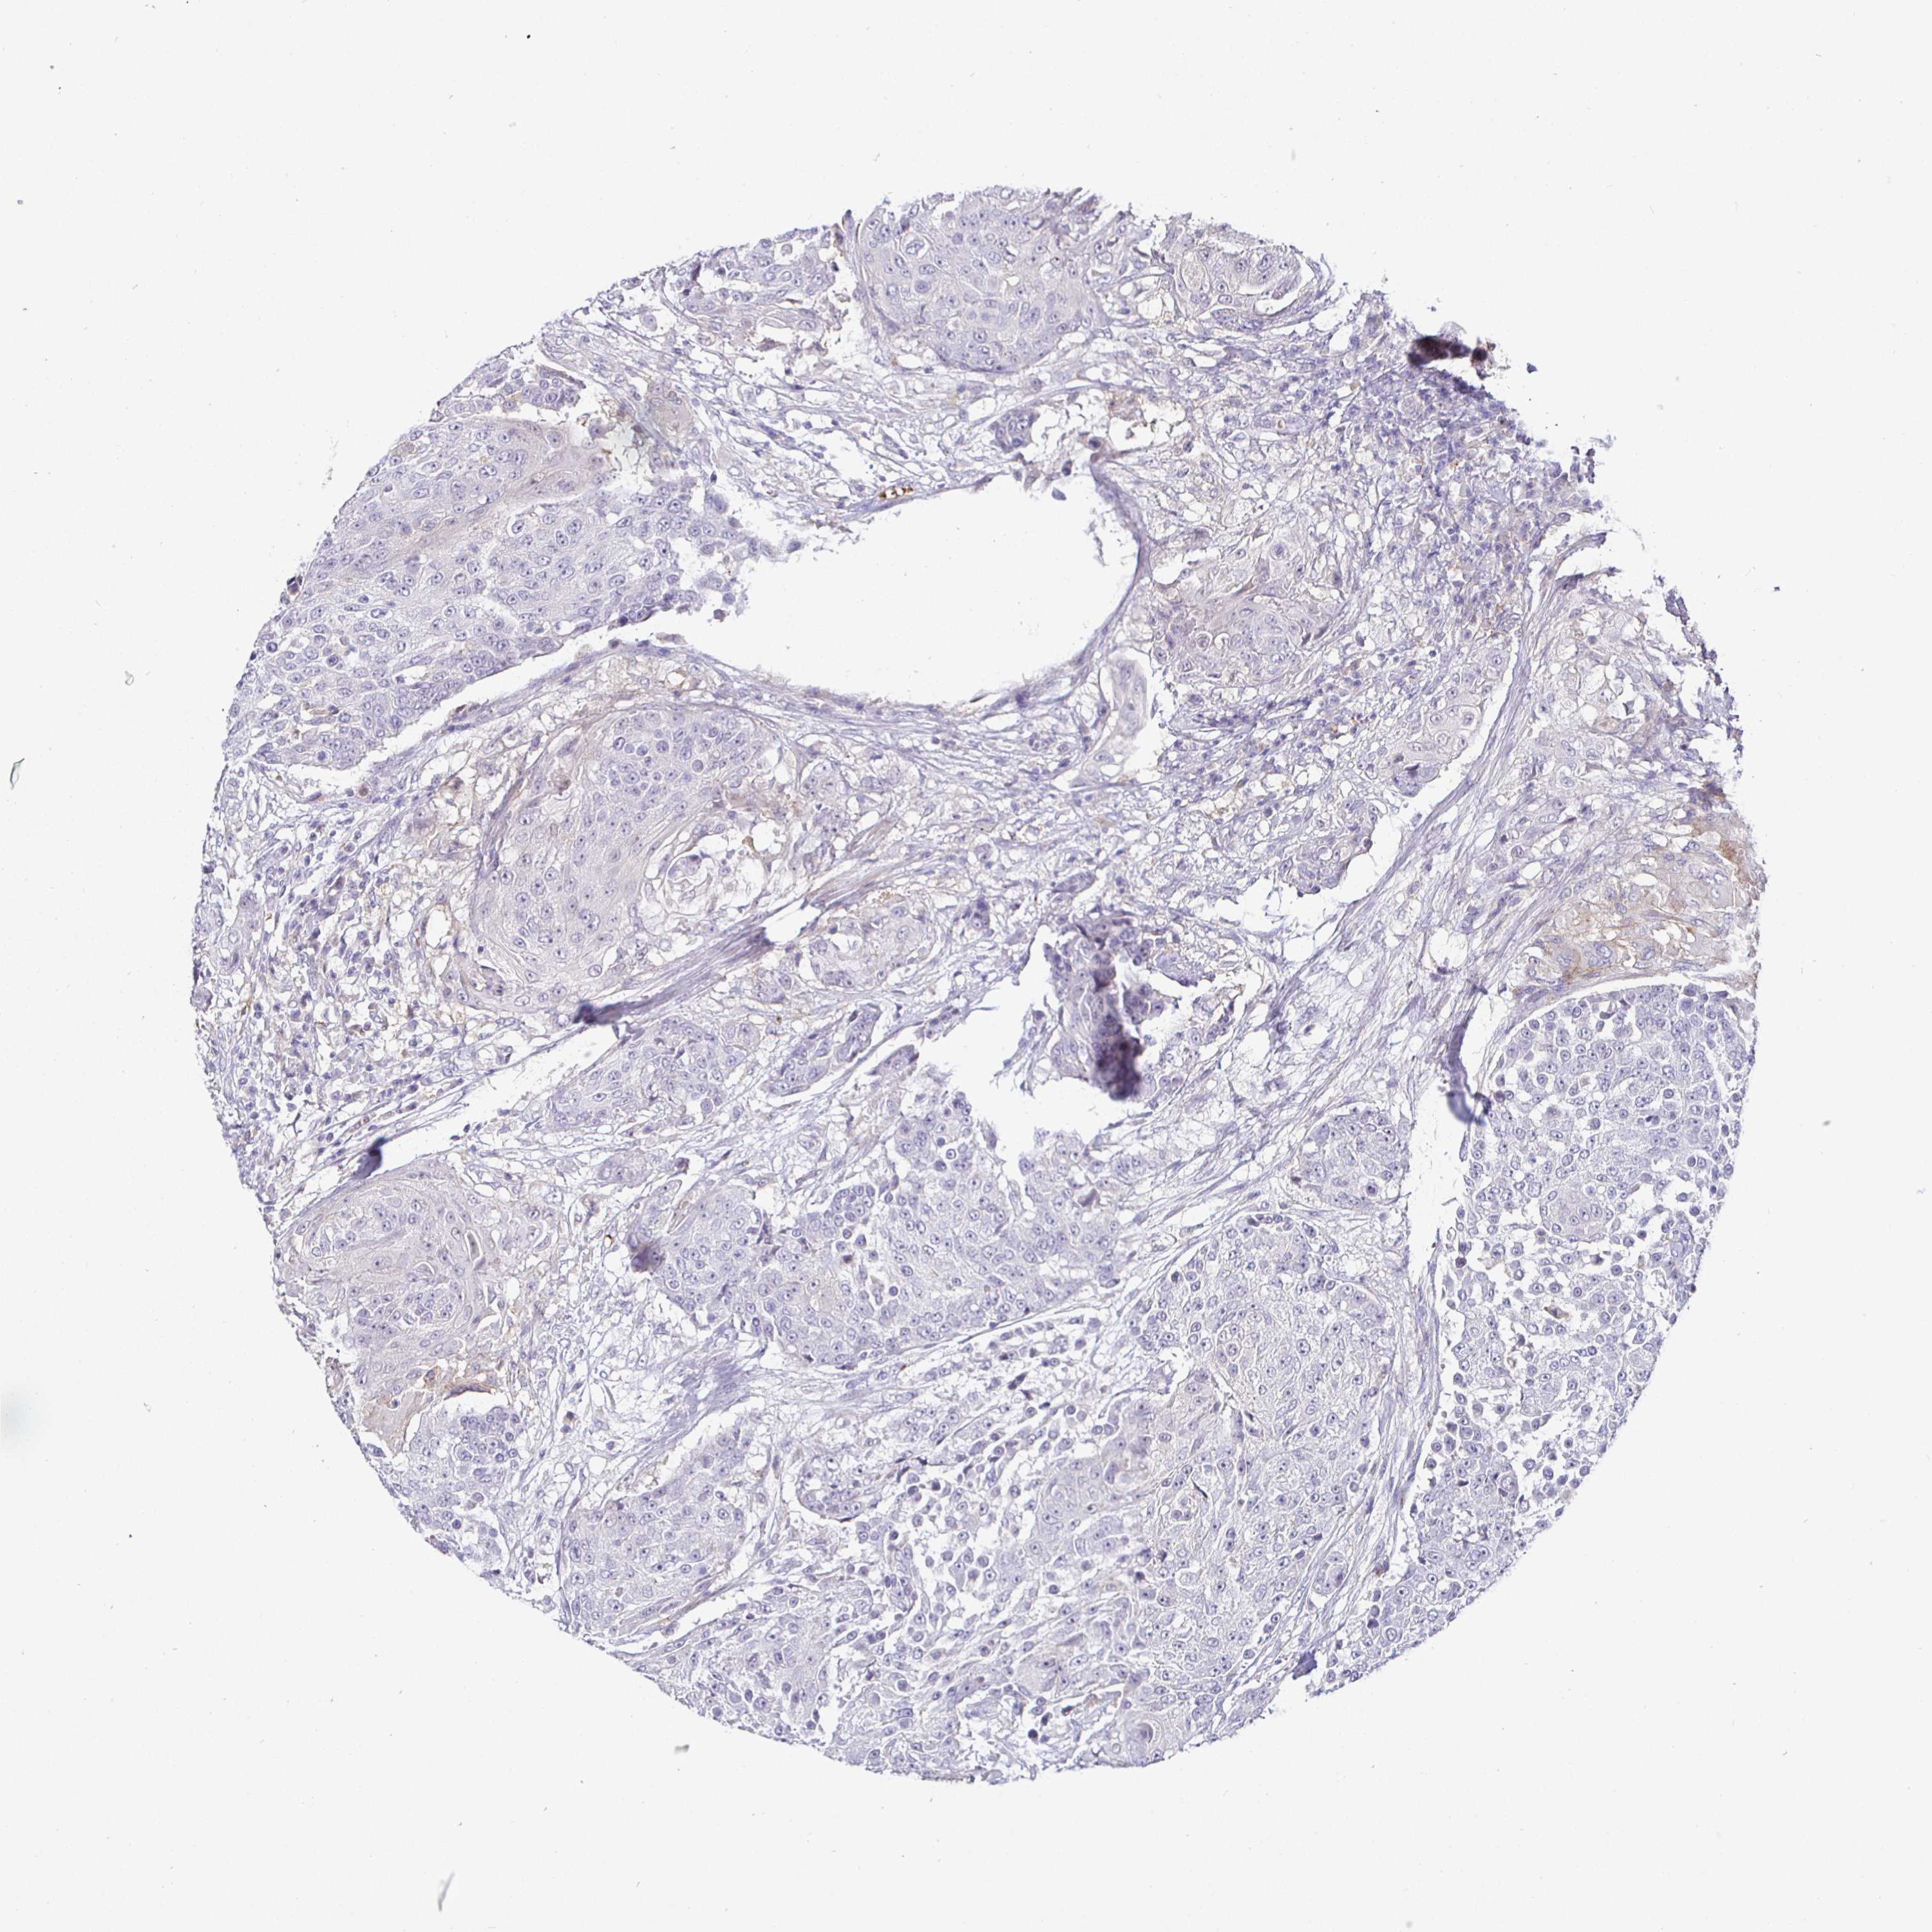

UROTHELIAL CANCER - Protein expressioni

A mouse-over function shows sample information and annotation data. Click on an image to view it in a full screen mode. Samples can be filtered based on level of antibody staining by selecting one or several of the following categories: high, medium, low and not detected. The assay and annotation is described here.

Note that samples used for immunohistochemistry by the Human Protein Atlas do not correspond to samples in the TCGA dataset.

Antibody stainingi

Antibody staining in the annotated cell types in the current human tissue is reported as not detected, low, medium, or high, based on conventional immunohistochemistry profiling in selected tissues. This score is based on the combination of the staining intensity and fraction of stained cells.

Each image is clickable and will lead to virtual microscopy that enables deeper exploration of all samples and also displays staining intensity scores, fraction scores and subcellular localization as well as patient and tissue information for each sample.

Antibody HPA054437

Antibody HPA058511

Antibody CAB002776

Antibody CAB015122

Staining

High

Medium

Low

Not detected

Intensity

Strong

Moderate

Weak

Negative

Quantity

>75%

75%-25%

<25%

None

Location

Nuclear

Cytoplasmic/membranous

Cytoplasmic/membranous,nuclear

Urothelial carcinoma, High grade

Urothelial carcinoma, Low grade

Urothelial carcinoma, NOS